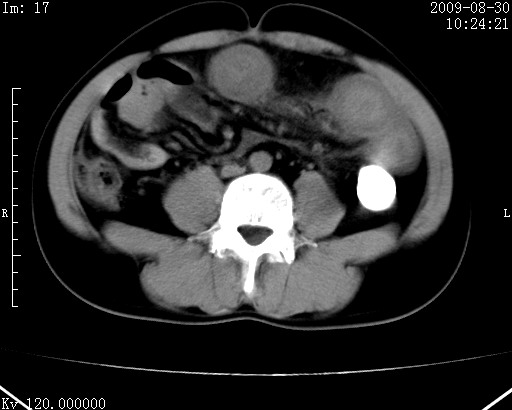

患者唐某,男31岁,已婚,本地务农。

自述入院前两天一次进食较多冷饮之后,出现阵发性上腹部疼痛,次日加剧伴恶心、呕吐,呕吐后症状稍减轻。食欲差。大便每天1-2次,量少,暗红色水样。小便赤。无畏寒、发热、咳嗽等呼吸道症状。无高血压及胃病史。

检查:体温、血压及脉搏正常.皮肤无黄染,浅表无淋巴结肿大。左腹肌紧张,左上腹有压痛,无反跳痛,可触及包块。

生化:钾、钠、氯、钙、ph正常,总胆红素和直接胆红素稍高,空腹血糖稍高。

尿淀粉酶:1256 u/l(正常60-401)。

血常规:wbc 22.4x109/l gr88% ly9.6%其余基本正常。

胃镜:急性胃炎。立位腹平片:未见异常。

下面是ct平扫,降结肠内是对比剂。

术前影像诊断:上段空肠急性缺血性坏死并腹水。建议手术治疗。

术中见上段空肠约70cm长范围坏死,从屈氏韧带远端约10cm处开始。坏死肠管肿胀变形变色,管壁明显环形增厚,部分聚成大肿块,无扭转和套叠。肠系膜上动脉分支内广泛泥沙状血栓。肠切除。

临床诊断:肠系膜上动脉梗塞并急性肠坏死。

开始时我们科也有人认为是套叠,最后统一意见,不考虑肠套。我们看到的“靶征”,“晕圈征”,“双圈征”实际上只是单根肠管的横断面。坏死肿胀后肠壁各层的密度不一样。

左侧腹小肠腔管壁明显增厚,部分内示靶征,走行异常,部分肠系膜绳样改变,肝包膜下及肠间较多液体密度,然梗阻近端肠腔积气不明显。

考虑;肠扭曲伴肠坏死。